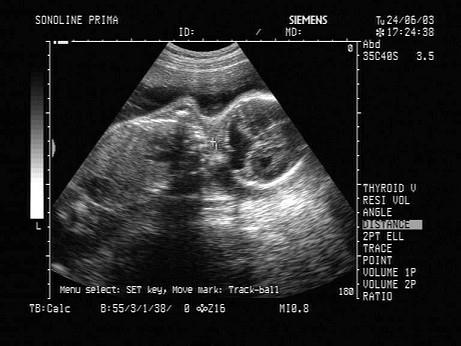

问题 女性,26岁,停经23周。产前B超检查如图,结合超声图像,最可能的诊断为?(?)

选项 A.前置胎盘 B.正常晚期妊娠 C.胎儿畸形,脑积水 D.胎儿畸形,腹壁裂 E.脉络膜囊肿

答案 C